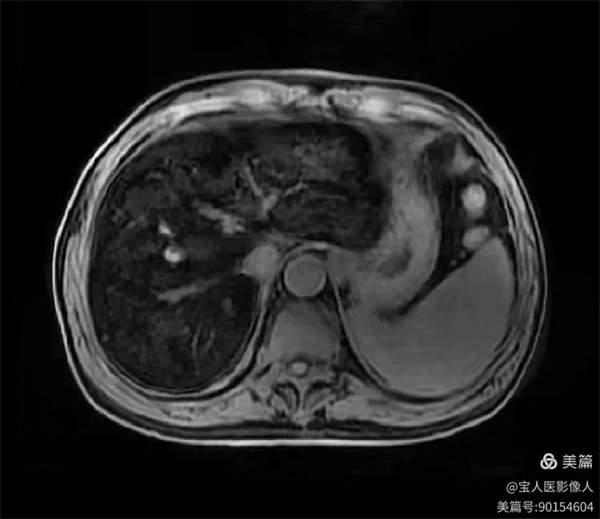

同、反相位,肝實質信號反相位略不均勻升高。